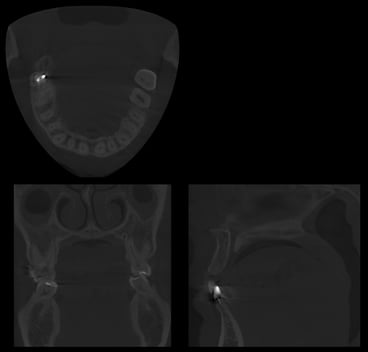

まっすぐにインプラントを埋入しようとすると上顎洞と呼ばれる鼻の空洞に突き抜けてしまいます。

このように傾斜すればしっかりした骨のあるところに埋入できますが、少しでもずれてしまうと関係ない組織にインプラントが突き抜けてしまいます。

そこで安全に傾斜埋入を行うためにまずCT撮影を行います。

CTの画像データをインプラント手術シュミレーションソフトに移し、使用するインプラントの種類や埋入角度などを決定します。

このシュミレーションソフトで決定した手術プランが正確にできるよう、手術ガイドを作成します。

実際に手術ガイドを用いてインプラント埋入を行います。

このように正確に傾斜してインプラントが安全に埋入できました。